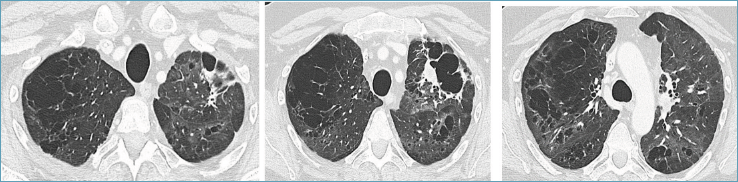

Poco più di un mese dopo la dimissione, la TC torace con contrasto (eseguita durante terapia domiciliare con prednisone) mostrava un quadro radiologico diffusamente migliorato (Fig. 2).

Figura 2.TC torace con contrasto a distanza di 9 giorni dalla dimissione.